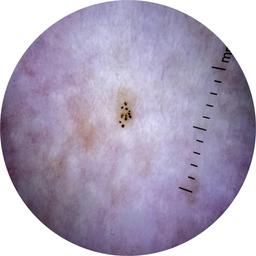

MEL-SELF - Dermoscopic

- Name: MEL-SELF - Dermoscopic

Dermoscopic lesion images (close-up views of benign and malignant lesions) from the MEL-SELF trial (the Melanoma Self Surveillance trial).